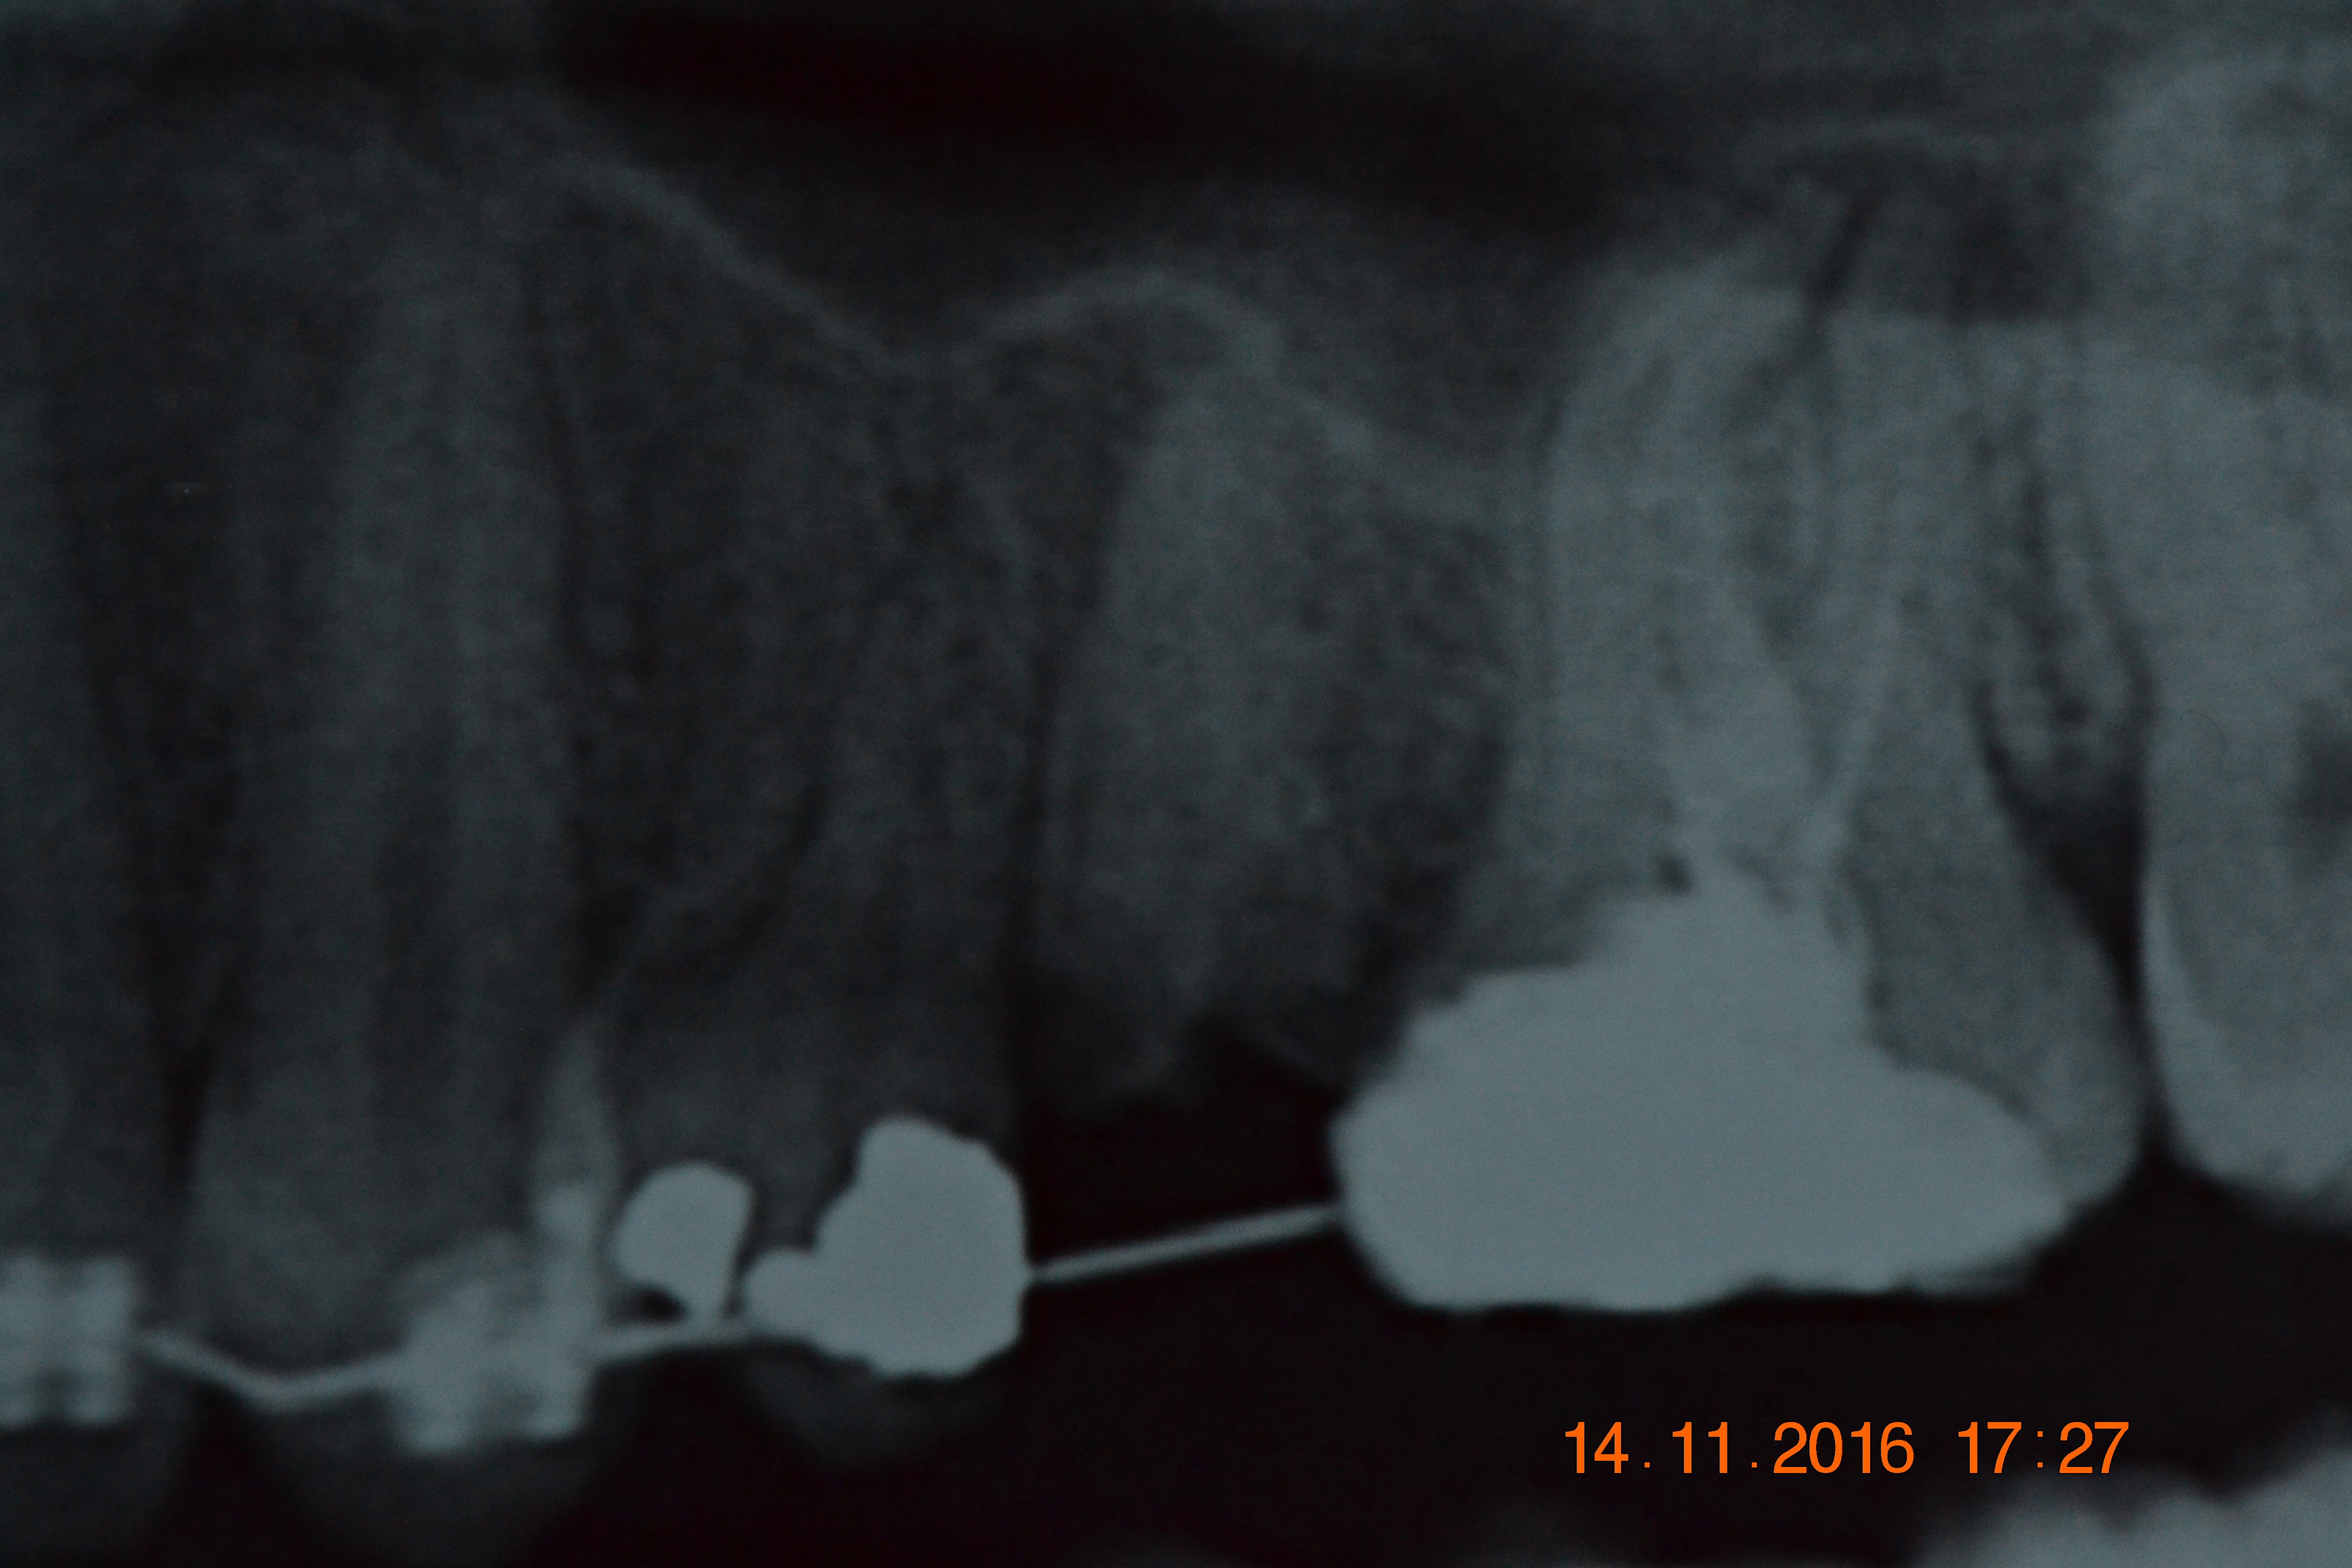

Em anamnese, nenhum desvio de base foi relatado. Em exame clínico e radiográfico foi constatada raiz residual do elemento 24 (Figura 1). O paciente foi pré-medicado com 2g de Amoxicilina e 4mg de Dexametasona, 1 hora antes do procedimento cirúrgico.

Figura 1: Radiografia Inicial